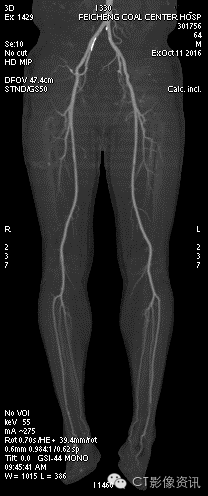

男,64岁,输尿管癌术后一年,长期化疗,近三日自感双下肢不适,来院就诊行盆腔CT增强及双下肢CTA,以除外双下肢动脉栓塞。

•   流速2.7ml/s(患者长期化疗,血管状态不好,采用较低流速),造影剂90ml,盐水20ml。

•   能谱扫描预重建55KeV图像,行VR及MIP观察。

•   下肢血管及其它远端血管CTA的成像一直是困扰影像科的难题,尤其对于长期化疗及其它血管状况不好的患者,尤其如此。

•   能谱CT成像的低KeV图像可以明显提高远端分级血管的显示能力,使低流速、低流量CTA扫描且清晰显示远端分级血管成为可能。